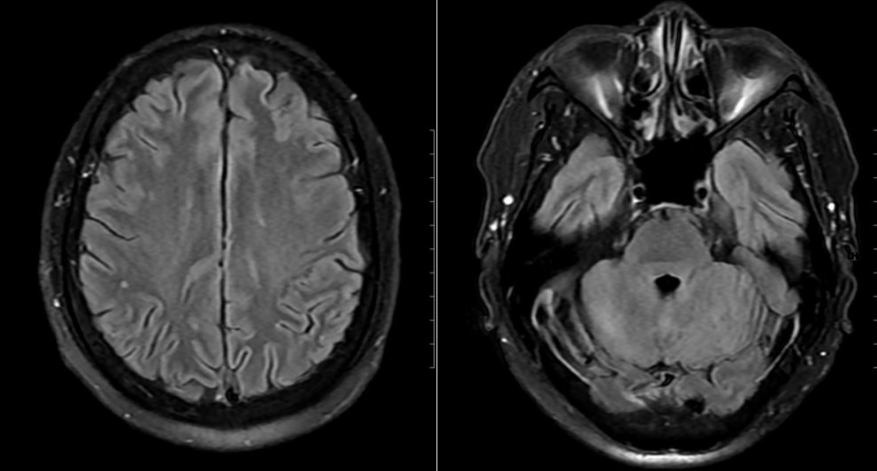

| Phim chụp của bệnh nhân. |

Mặc dù chưa có biểu hiện thần kinh rõ ràng, bệnh nhân vẫn được chọc dò dịch não tủy để loại trừ biến chứng. Kết quả ghi nhận dịch não tủy tăng tế bào và protein, phản ứng Pandy dương tính, xác định viêm não, màng não. Hình ảnh MRI sọ não còn phát hiện ổ tổn thương nhỏ tại thùy chẩm trái.

Sau 24 giờ, bệnh nhân cắt sốt, thể trạng cải thiện rõ rệt. Sau 15 ngày điều trị tích cực, các xét nghiệm và hình ảnh học cho thấy tổn thương đã hồi phục hoàn toàn, bệnh nhân xuất viện trong tình trạng ổn định, không để lại di chứng thần kinh.